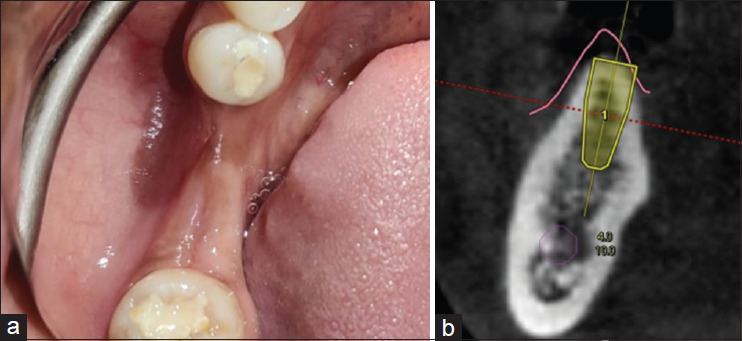

Conventional alveolar ridge splitting (ARS) technique involves a significant risk which may prove problematic. This case report presents the first documented application of dynamic navigation system (DNS)-guided ARS, demonstrating a precise approach to implant placement in a challenging anatomical scenario. A 37-year-old partially edentulous patient presented with missing mandibular posterior teeth. Clinical examination revealed a deficient alveolar ridge. Cone-beam computed tomography evaluation showed a Siebert's Class I resorbed ridge with 2.5 mm width and bone density ranging from 870 to 1040 Hounsfield Units in the #46 and #47 regions. Creating and designing three-dimensional virtual guide slits and implant planning using DNS were done in patient with insufficient bone width in the mandibular molar region. Piezoelectric ARS, osteotomy preparation with implant placement was done. 0.70 and 0.26 mm deviations at #46 and 0.50 and 0.01 mm deviations at #47 were observed at implant entry and implant apex, respectively. The angular deviations were optimal. ARS using real-time navigation appears to be an efficient and promising technique.